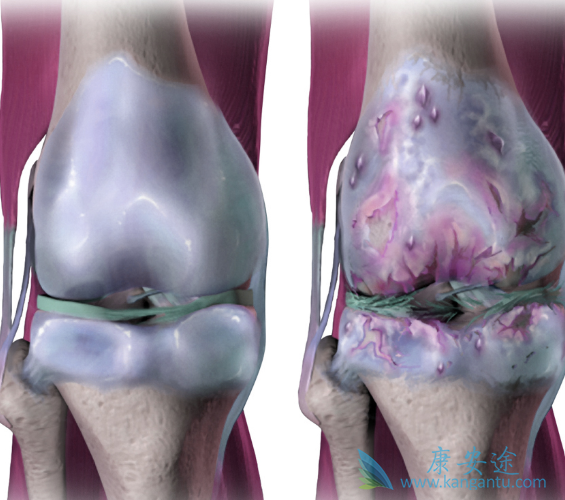

辉瑞与合作伙伴礼来近日公布了非阿片类新型止痛药tanezumab治疗骨关节炎(OA)III期临床研究(A4091058)的顶线结果。该研究旨在比较两种剂量tanezumab(2.5mg和5mg)与非甾体抗炎药(NSAID)治疗中度至重度髋关节或膝关节OA患者56周的疗效和长期(80周)安全性。结果显示,仅高剂量tanezumab表现出显著疗效,但同时关节安全事件发生率明显升高。

A4091058是一项随机、双盲、阳性药物对照、多中心、平行组研究,在中重度骨关节炎患者中开展,评估了tanezumab皮下注射给药相对于口服NSAID治疗56周的安全性和疗效。研究在全球(包括美国、欧洲、亚洲、拉丁美洲)开展,共入组3021例患者,这些患者对对乙酰氨基酚和曲马多或阿片类药物(或不愿服用阿片类药物)治疗疼痛缓解不足或对这些药物不耐受,在筛查进入研究前接受稳定剂量NSAID治疗并且在随机化分组前至少从中获得了一定治疗受益。患者平均患有OA约8年时间,基线为西安大略和麦克马斯特大学骨关节炎指数(WOMAC)疼痛评分7分(总分10分),研究开始时患者还报告疼痛对其日常生活中的功能产生了显著的影响。